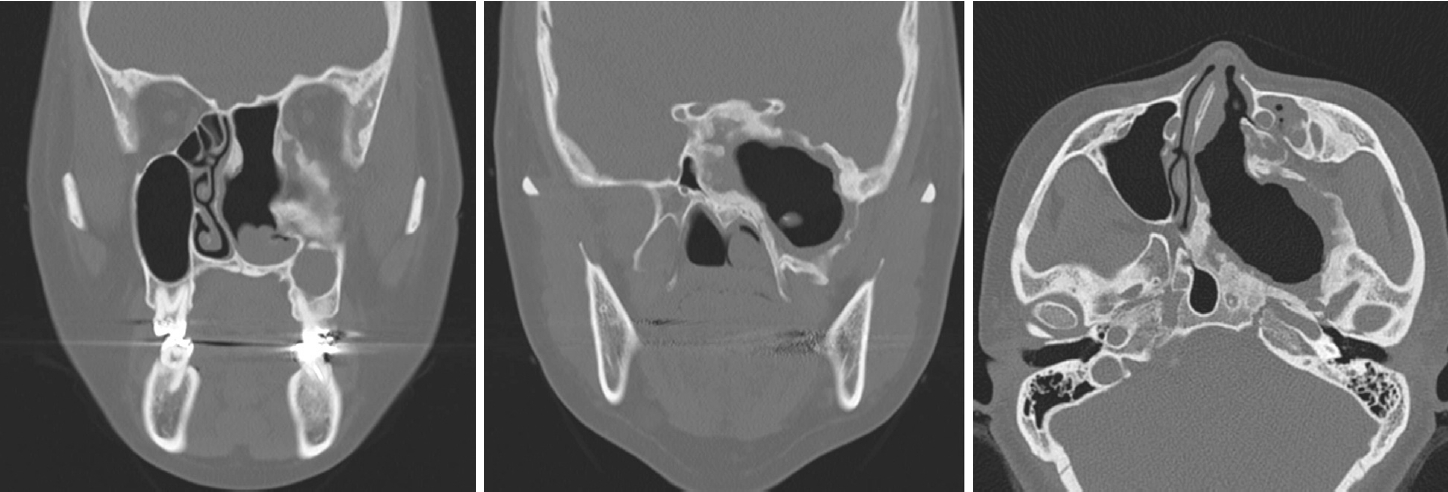

이에 시행한 전산화단층촬영 결과 좌측 사골동을 중심으로 하여 접형동, 익구개와, 익판을 침범한 골성 병변이 관찰되었다. 병변의 경계는 명확하였고 특징적인 간유리음영(ground-glass opacity)을 보여 섬유 이형성증을 의심할 수 있었다. 병변의 크기는 7 cm에 달하였고 그 내부에는 격막이 쳐진 낭성병변이 관찰되었다. 병변의 종괴 효과로 인한 좌측 안와 종이판의 침식과 상악동의 저형성 및 비중격의 우편위가 있었다(Fig. 2).

NotesAuthor Contribution Conceptualization: Seung Heon Kang, Hyun Jik Kim. Data curation: Seung Heon Kang, Hyunkyung Cha, Seung Cheol Han. Formal analysis: Seung Heon Kang, Hyun Jik Kim. Funding acquisition: Seung Heon Kang. Investigation: Seung Heon Kang. Methodology: Seung Heon Kang. Project administration: Seung Heon Kang. Resources: Seung Heon Kang. Supervision: Hyun Jik Kim. Validation: Seung Heon Kang. Visualization: Seung Heon Kang. Writing—original draft: Seung Heon Kang. Writing—review & editing: Seung Heon Kang. Fig. 1.Endoscopic finding of expansile extruding mass covered with normal mucosa in left middle meatus. Fig. 2.Left ethmoid fibrous dysplasia combined with mucocele (A) eroded lamina papyracea (B) involvement of pterygoid plates (C) hypoplastic left maxillary sinus and right septal deviation. Fig. 3.Endoscopic findings of operation (A) brownish content spilled out from the mucocele (B) visualization of septated mucoceles (asterisks) after removal of anterior wall of fibrous dysplasia (C) after marsupialization. Fig. 4.Histopathologic findings of FD, pathologic report of FD: osteoid trabeculae that are narrow, curvilinear or irregularly-shaped are arranged haphazardly in a background of dense fibroblastic stroma (hematoxylin and eosin, original magnification ×20). FD: fibrous dysplasia. REFERENCES1. Weinstein LS, Shenker A, Gejman PV, Merino MJ, Friedman E, Spiegel AM. Activating mutations of the stimulatory G protein in the McCune-Albright syndrome. N Engl J Med 1991;325(24):1688-95.